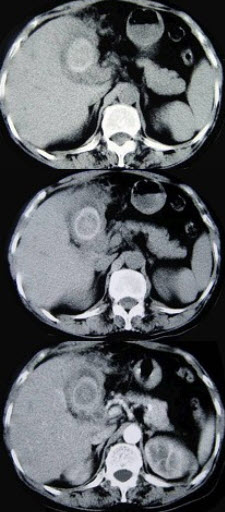

17、单项选择题

男,52岁,右上腹隐痛1年,巩膜黄染,皮肤不黄,CT检查如图,最可能的诊断为()

A.原发性肝癌